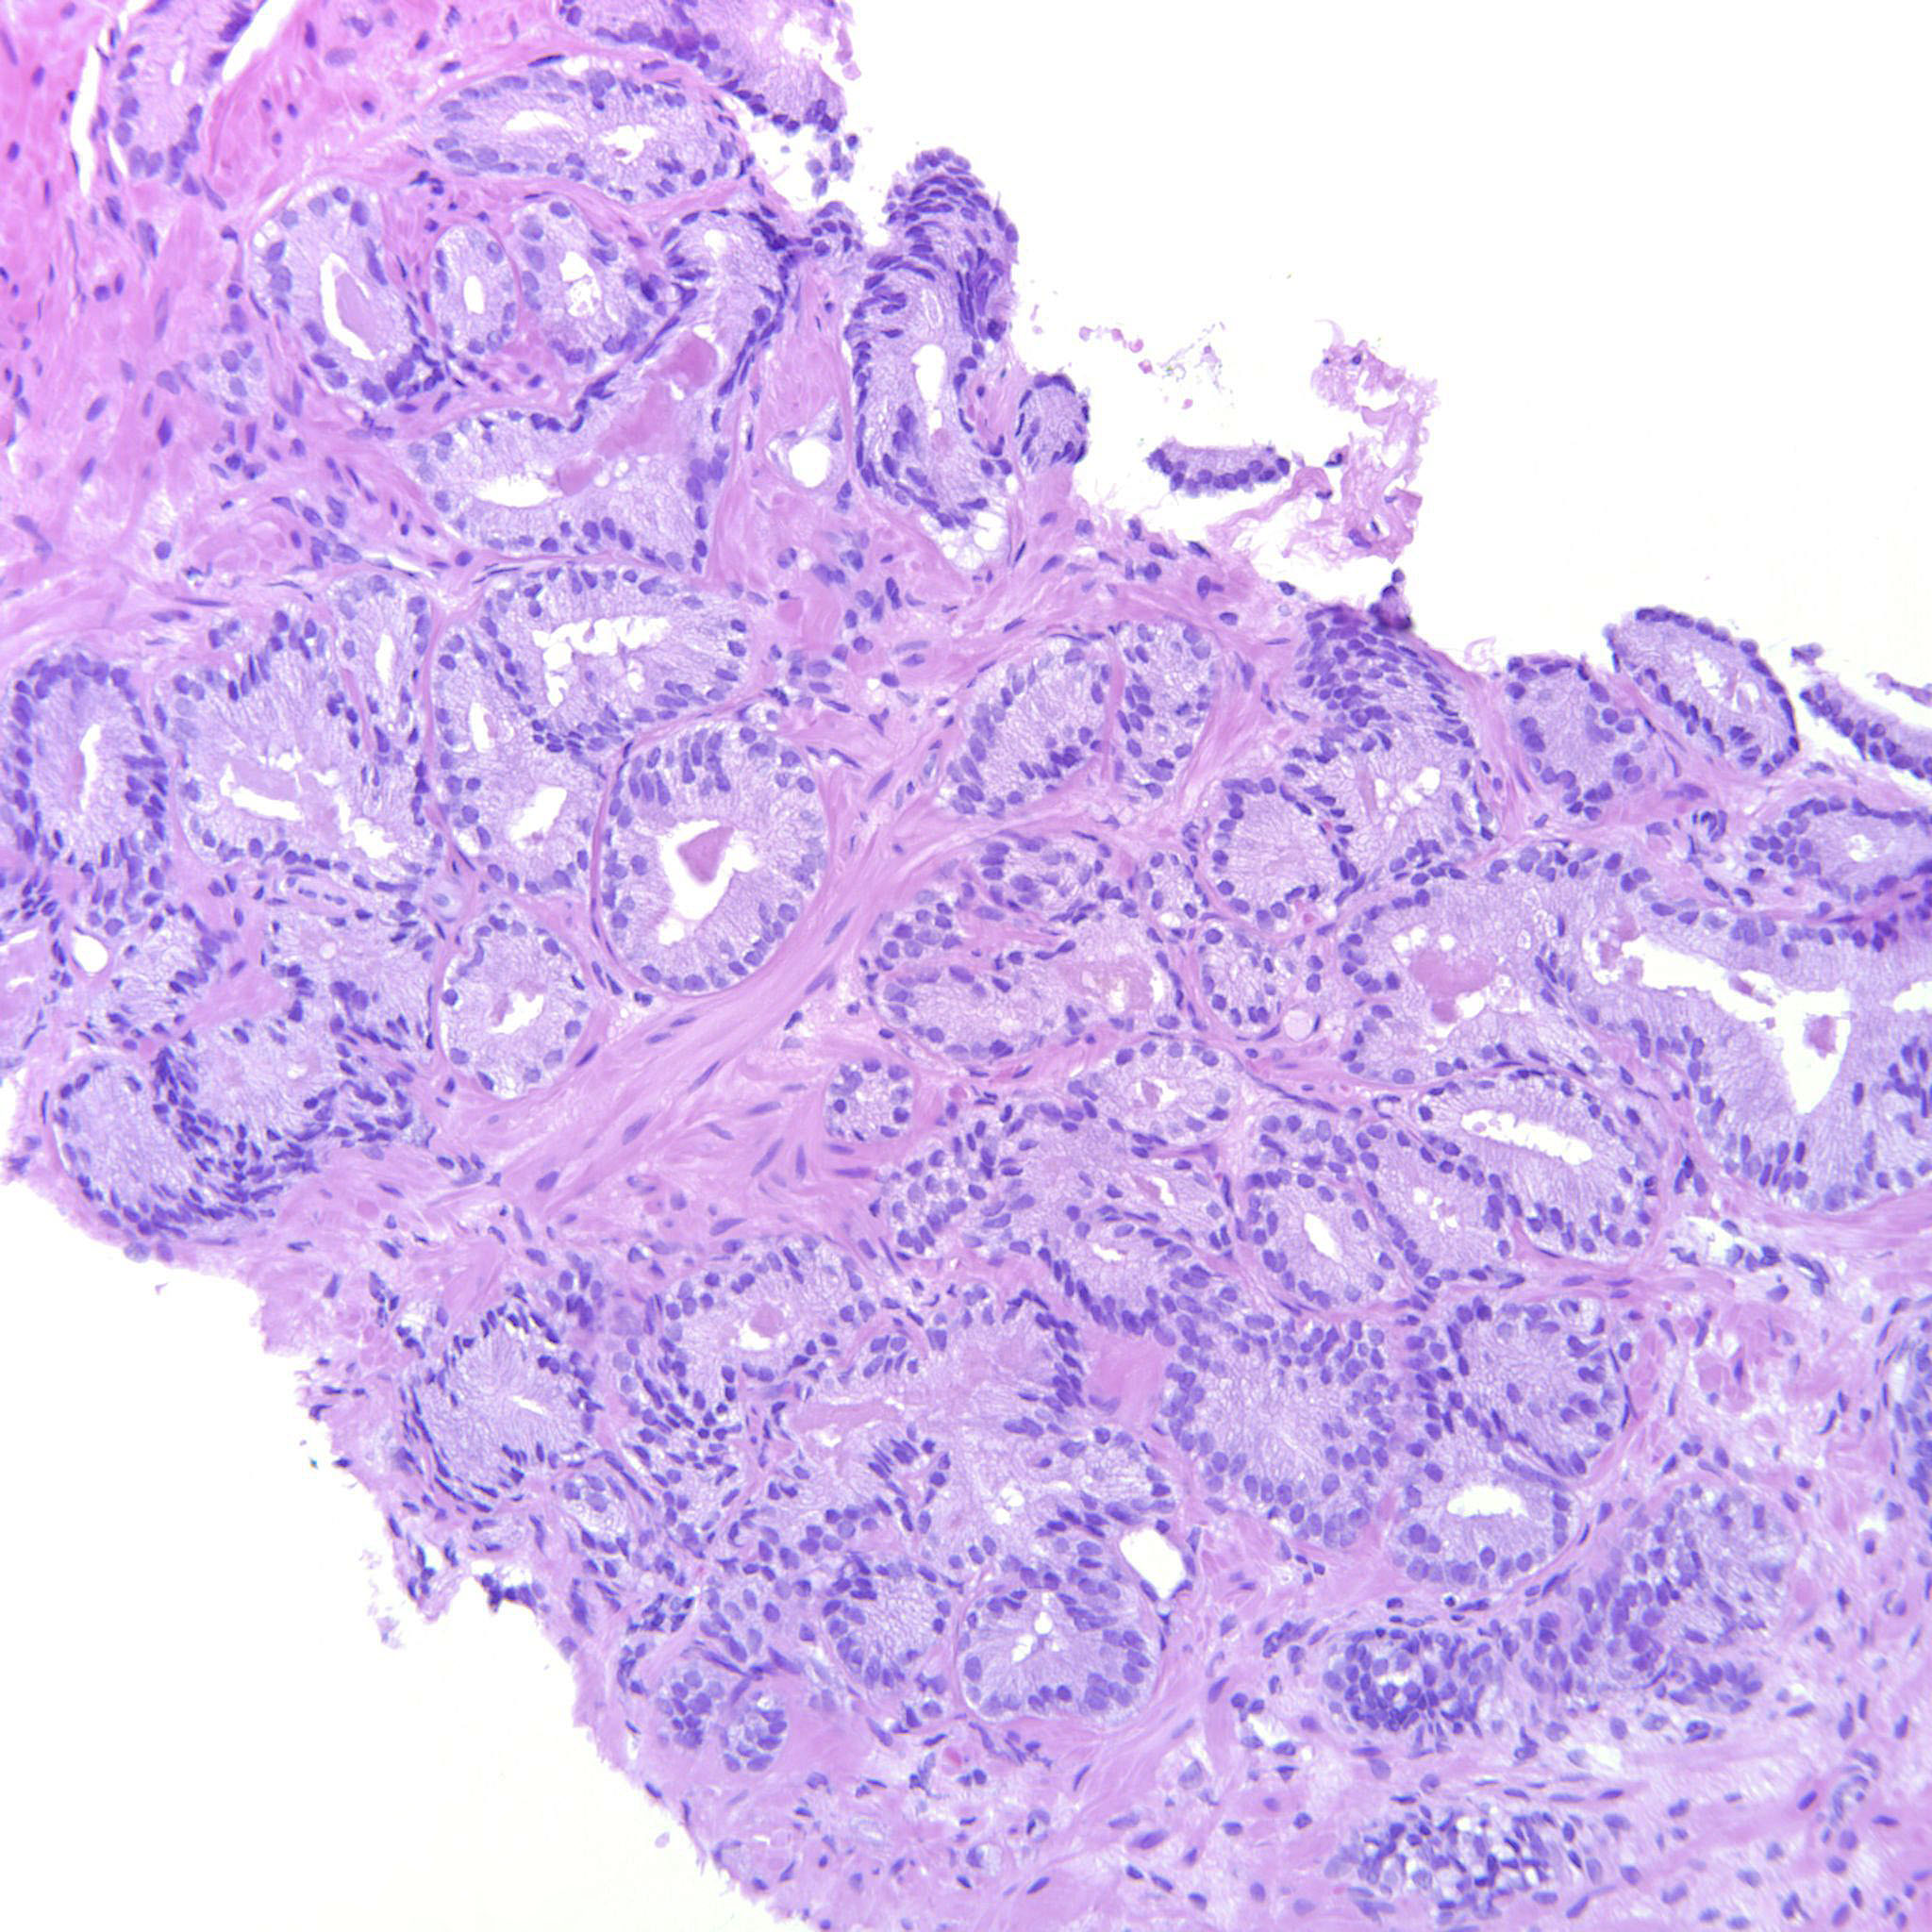

Prostate cancer grading

Case ID: 480